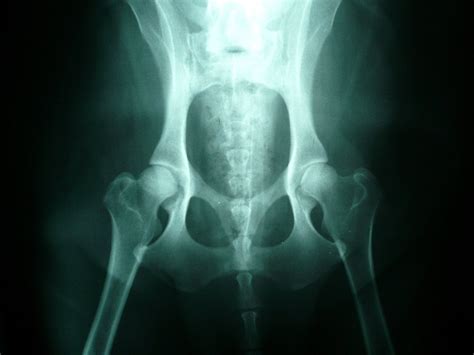

Ako pracovné plemeno, nemecký ovčiak môže trpieť dedičnými ochoreniami. Medzi najčastejšie patria dysplázia bedrového a lakťového kĺbu, degeneratívna myelopatia, torzia žalúdka, exokrinná pankreatická insuficiencia a kožné alergie. Dôležitá je preto správna výživa, primerané množstvo pohybu a pravidelné veterinárne prehliadky. V oficiálnom štandarde sú vylúčené vážne exteriérové a povahové vady. Odporúča sa starostlivo vyberať šteniatko od zodpovedného chovateľa, ktorý dbá na zdravotný stav svojich psov a vykonáva potrebné genetické testy.